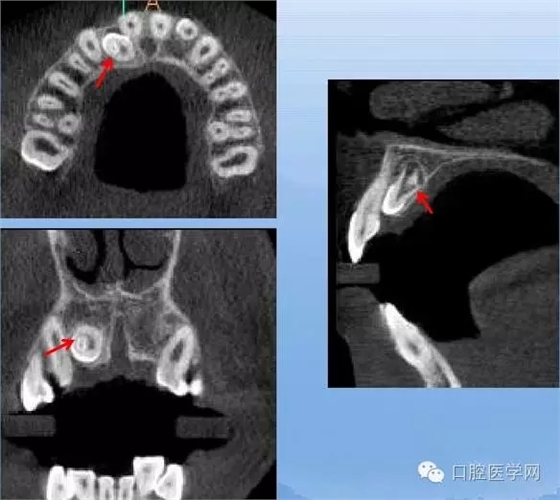

額外牙

X線表現(xiàn):最多見(jiàn)于上頜兩中切牙之間;圓錐形,根短小;拍攝X線片可確定額外牙的數(shù)目、位置、形態(tài)與鄰牙的關(guān)系。